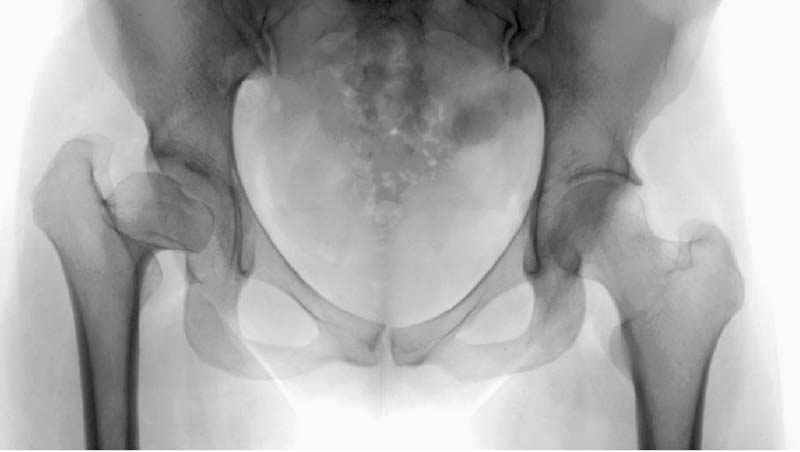

Мною произведены измерения на 290 рентгенограммах ТБС у молодых лиц обоего пола (средний возраст их 26.919 лет) без признаков патологии означенного сустава. Согласно точным расчетам плечо массы тела в среднем составило 107.685 мм (расстояние от центра головки бедренной кости до средней линии тела). Согласно тем же точным расчетам плечо силы реакции связки головки бедра равняется в среднем 35.190 мм (расстояние от центра головки бедренной кости до дна ямки вертлужной впадины, где прикрепляется проксимальный конец связки головки бедра). Соответственно плечо веса тела относится к плечу силы реакции связки головки бедра как 1:3,060, это если быть точным… Я допускаю, что есть проекционные искажения, эффект увеличения изображения на рентгенограмме, погрешности в измерениях, индивидуальная изменчивость размеров, быть может я недостаточное количество суставов обмерил, точку проксимального крепления связки головки бедренной кости на рентгенограмме не видно, а линия действия ОЦМ в одноопорном ортостатическом положении смещается от центра в сторону ТБС на разную величину, обусловленную антропометрическими особенностями и т.д.… именно поэтому в своем сообщении я указал соотношение 1:3, и назвал его приблизительным».